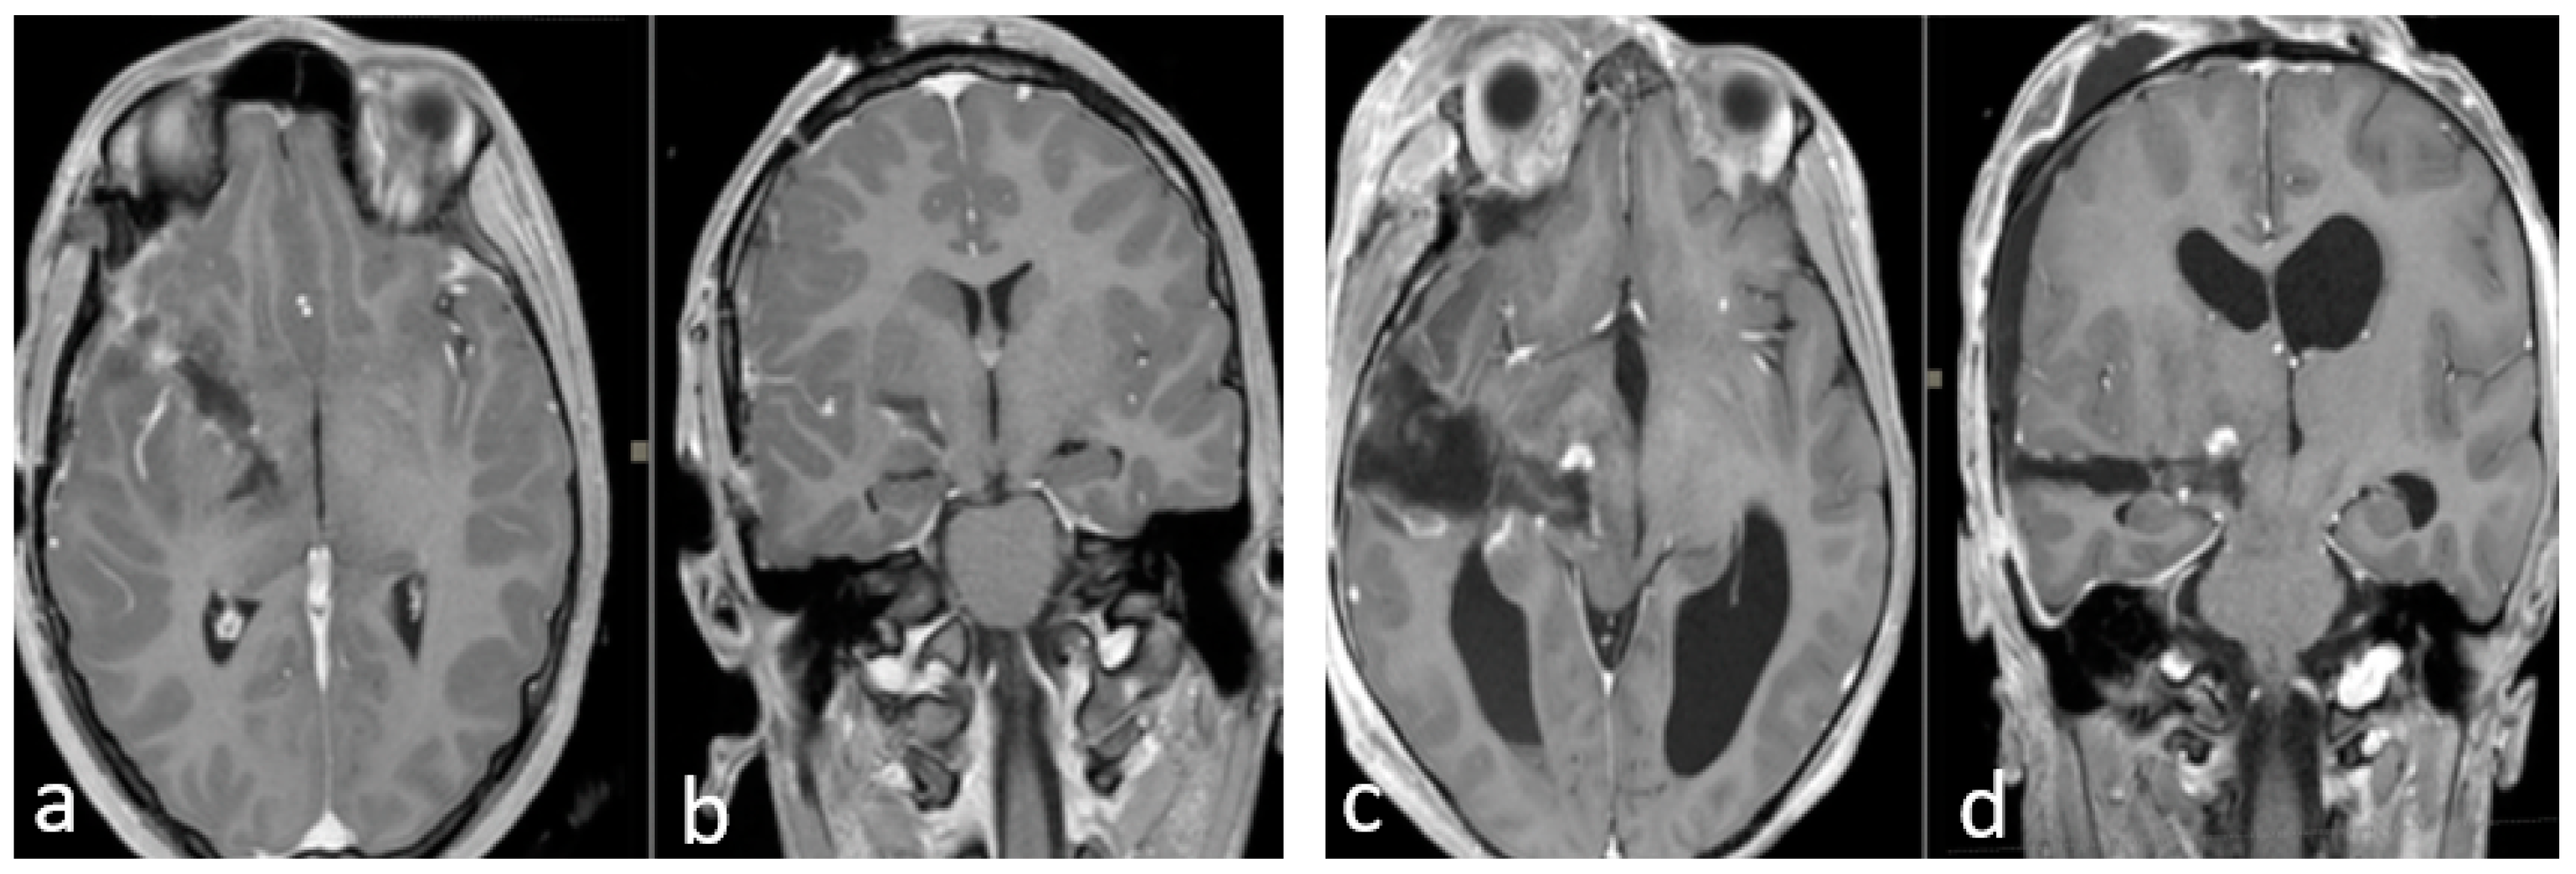

Finally, in all cases, we performed a postoperative brain MRI with gadolinium within 24 h of the surgery (Figure 3).

Figure 3.

(a–d) Early postoperative brain MRI with gadolinium. (a,b) An early postoperative brain MRI, T1-weigthed with gadolinium in the axial (to the left) and coronal plane (to the right), for Case A in Figure 2. (c,d) An early post operative MRI, T1-weigthed with gadolinium, for Case B in Figure 1. In detail: In accordance with the nTMS data, we performed a transsylvian approach for Case A (a,b) obtaining a gross total resection (GTR). In Case B (b–d), we performed a trans-temporal approach, obtaining a subtotal resection (STR).

The main surgical corridor used was the transsylvian approach (Case A–E–F–G–H). In two cases, we used the transcortical transtemporal route (Case B–C), and in one case, we used a posterior parietal approach (Case D) due to the greater posterior parietal development of the lesion. We achieved GTR in two cases (Case A–Case C), STR in five (Case B–E–F–G–H), and PR in one (Case D).